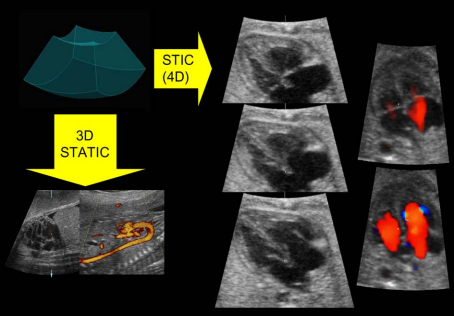

با پیشرفت علم و پزشکی، اکوکاردیوگرافی مادرزادی با روش های سونوگرافی قلب جنین 2D - 3D - 4D (STIC)، سونوگرافی داپلر رنگی... می تواند عیوب غیر طبیعی را تشخیص دهد. علاوه بر این، این روش ها مزایای بزرگ دیگری را هم برای نوزادان و هم برای والدین به همراه دارد:

سونوگرافی 4 بعدی (چهار بعدی). سونوگرافی 4 بعدی از پروب مخصوصی استفاده می کند که قادر به گرفتن یک سری تصاویر از قلب جنین در حال تپش است. این تصاویر را می توان در چندین هواپیما به طور همزمان روی صفحه نمایش مشاهده کرد. همچنین می توان آنها را بازسازی کرد تا تصویر واقعی تری از قلب جنین ارائه کند. این به دکتری که معاینه را انجام می‌دهد کمک می‌کند بیماری‌هایی را که می‌تواند بر قلب نوزاد تأثیر بگذارد، بهتر درک کند و تشخیص دهد.

ناهنجاری های مشکوک را می توان با استفاده از چندین روش تصویربرداری ارزیابی کرد، اگرچه معاینه را می توان برای ناهنجاری های خاص قلبی جداگانه ارزیابی کرد . سونوگرافی در مقیاس خاکستری بلادرنگ و تکنیک های سونوگرافی داپلر مکمل (به عنوان مثال طیفی و رنگی) اغلب استفاده می شود. اکوکاردیوگرافیM-mode و سونوگرافی داپلر نیز ابزارهای مهمی برای تجزیه و تحلیل دیس ریتمی قلب جنین هستند. نتایج اضافی، از سونوگرافی سه بعدی (3 بعدی) و 4 بعدی، ممکن است اطمینان تشخیصی را برای توصیف دقیق برخی از ضایعات پیچیده افزایش دهد.

یک تصویر دو بعدی (مطالعه 2 بعدی و 3 بعدی) از قلب جنین می سازد که همانطور که در ویدیوی بالا سمت چپ مشاهده می شود، روی صفحه نمایش داده می شود و قلب طبیعی جنین را با 4 حفره نشان می دهد.

جریان خون قلب جنین را مطالعه می کند (مطالعه داپلر طیفی و داپلر رنگی) همانطور که در ویدیوی سمت چپ بالا مشاهده می شود که قوس آئورت را با جریان خون (رنگ قرمز) نشان می دهد.